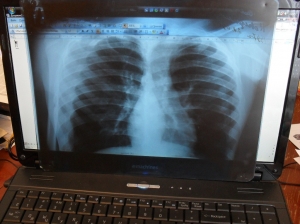

Для контроля над заболеваемостью взрослое население города должно ежегодно проходить обследование на флюорографе.